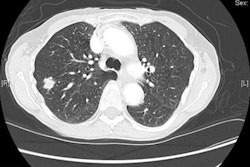

The U.S. National Lung Screening Trial (NLST) in 2011 compared two ways of detecting lung cancer: low-dose CT and standard chest x-ray.

In her talk, Nawaz outlined the primary study findings of NLST, which revealed there is a 20% lower risk of lung cancer mortality with low-dose CT and a 6.7% reduction in all-cause mortality with the modality. As a result, 7.6% of all U.S. lung cancer deaths each year could be averted, suggesting there is adequate evidence to indicate annual screening with low-dose CT can prevent a substantial number of lung cancer deaths among high-risk patients.

As a result of the NLST study, a number of different guidelines have recommended annual screening with low-dose CT for select patients, with most suggesting those in an age range between 55 and 80 years old with a history of heavy smoking or individuals who have quit within 15 years, she continued.

The main risk of screening is overdiagnosis, as positive findings were detected in 24.2% of low-dose CT studies, with further studies revealing that more than 95% of these were benign on further examination, according to Nawaz. Interestingly, lung cancer screening has only an 18% overdiagnosis rate, compared with 30% to 54% with breast cancer screening and 29% to 44% with prostate cancer screening.

In addition, subsequent retrospective analysis of the results from the International Early Lung Cancer Action Program (I-ELCAP) showed that increasing the threshold size at which nodules are worked up to 6 mm (rather than 4 mm in the NLST study) reduced the number of false-positive findings by half without compromising cancer detection.